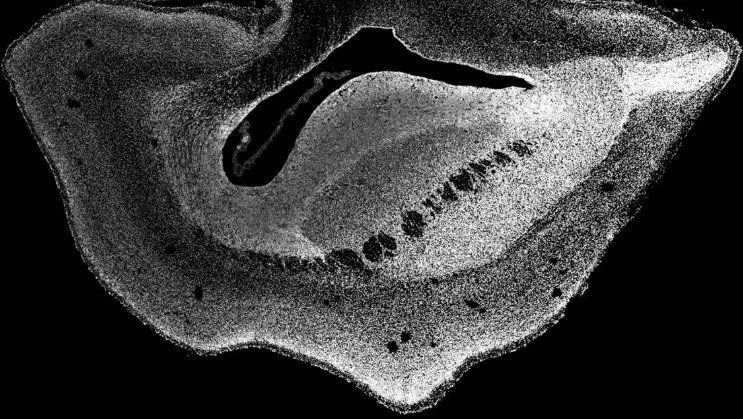

"De hecho, descubrimos que el neocórtex del cerebro del tití común se agrandó y la superficie del cerebro se plegó", dijo Michael Heide, autor del estudio que fue publicado en la revista Science este julio y que plantea ciertas cuestiones éticas sobre la ingeniería genética, según consignó el "New York Post".

Los investigadores revelaron que los cerebros de los fetos pronto desarrollaron neocórtex más grandes y avanzados, un área que en los humanos constituye la mayor parte de la corteza cerebral.

Como resultado, concluyeron que el gen ARHGAP11B, específico de los humanos, pudo haber causado la expansión del neocórtex en el curso de la evolución humana.

El neocórtex humano, una fracción del cerebro que juega un papel importante en los procesos del pensamiento, el lenguaje y la percepción, es la parte evolutivamente más joven de la corteza cerebral, y en la especie humana es aproximadamente tres veces más grande que el de los chimpancés.